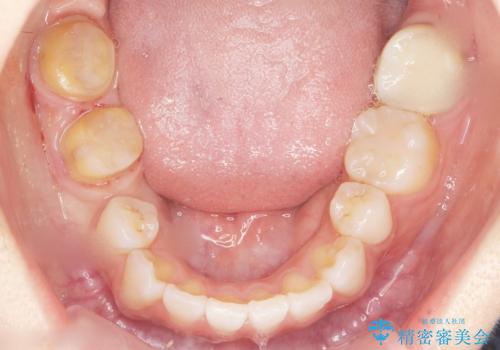

- 奥歯の隙間を治したいとご希望された患者様です。

学生時代に舌側矯正されていたものの、通院が大変になり治療を途中でやめてしまい、奥歯の間に隙間が残ってしまったそうです。

矯正せずに早く治したいという強いご希望とう蝕があることから、セラミッククラウンによる補綴治療で隙間を閉じることにしました。

- ¥242,000 (仮歯・クラウン×2本) ※税込費用は治療当時の料金となります